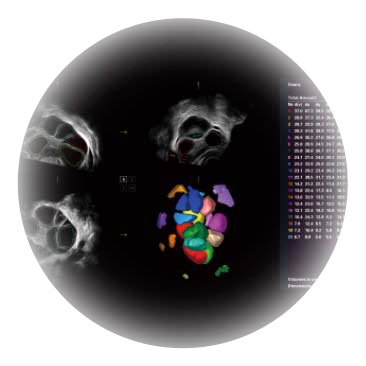

自动获取标准切面,自动完成测量,帮助医生快速完成检查,同时提升测量准确性。

卵泡结构的自动识别和测量,可显示多组测量数据。